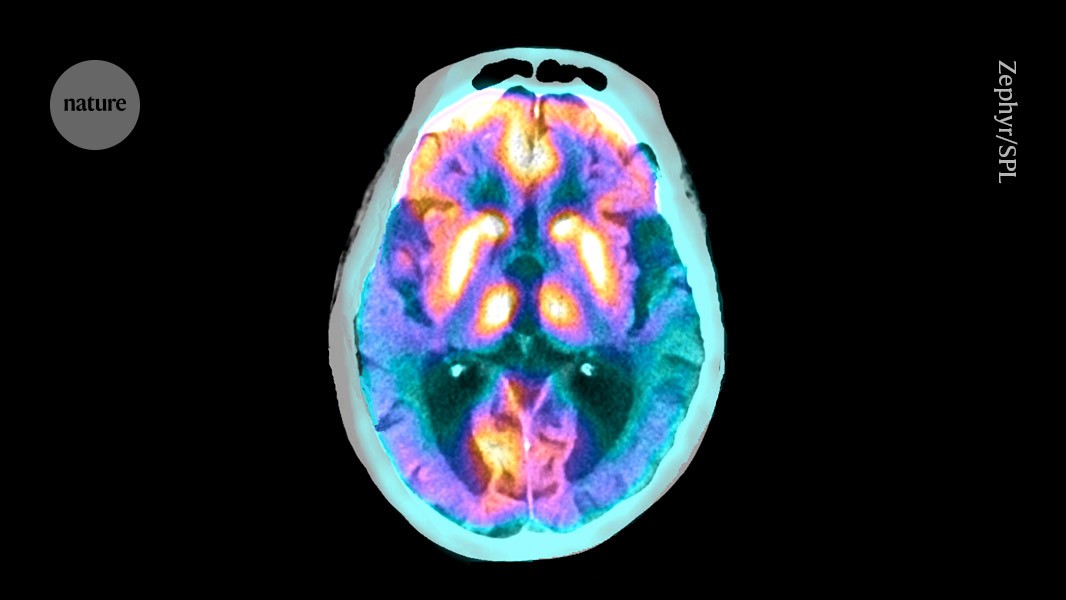

Credit: Zephyr/Science Photo Library